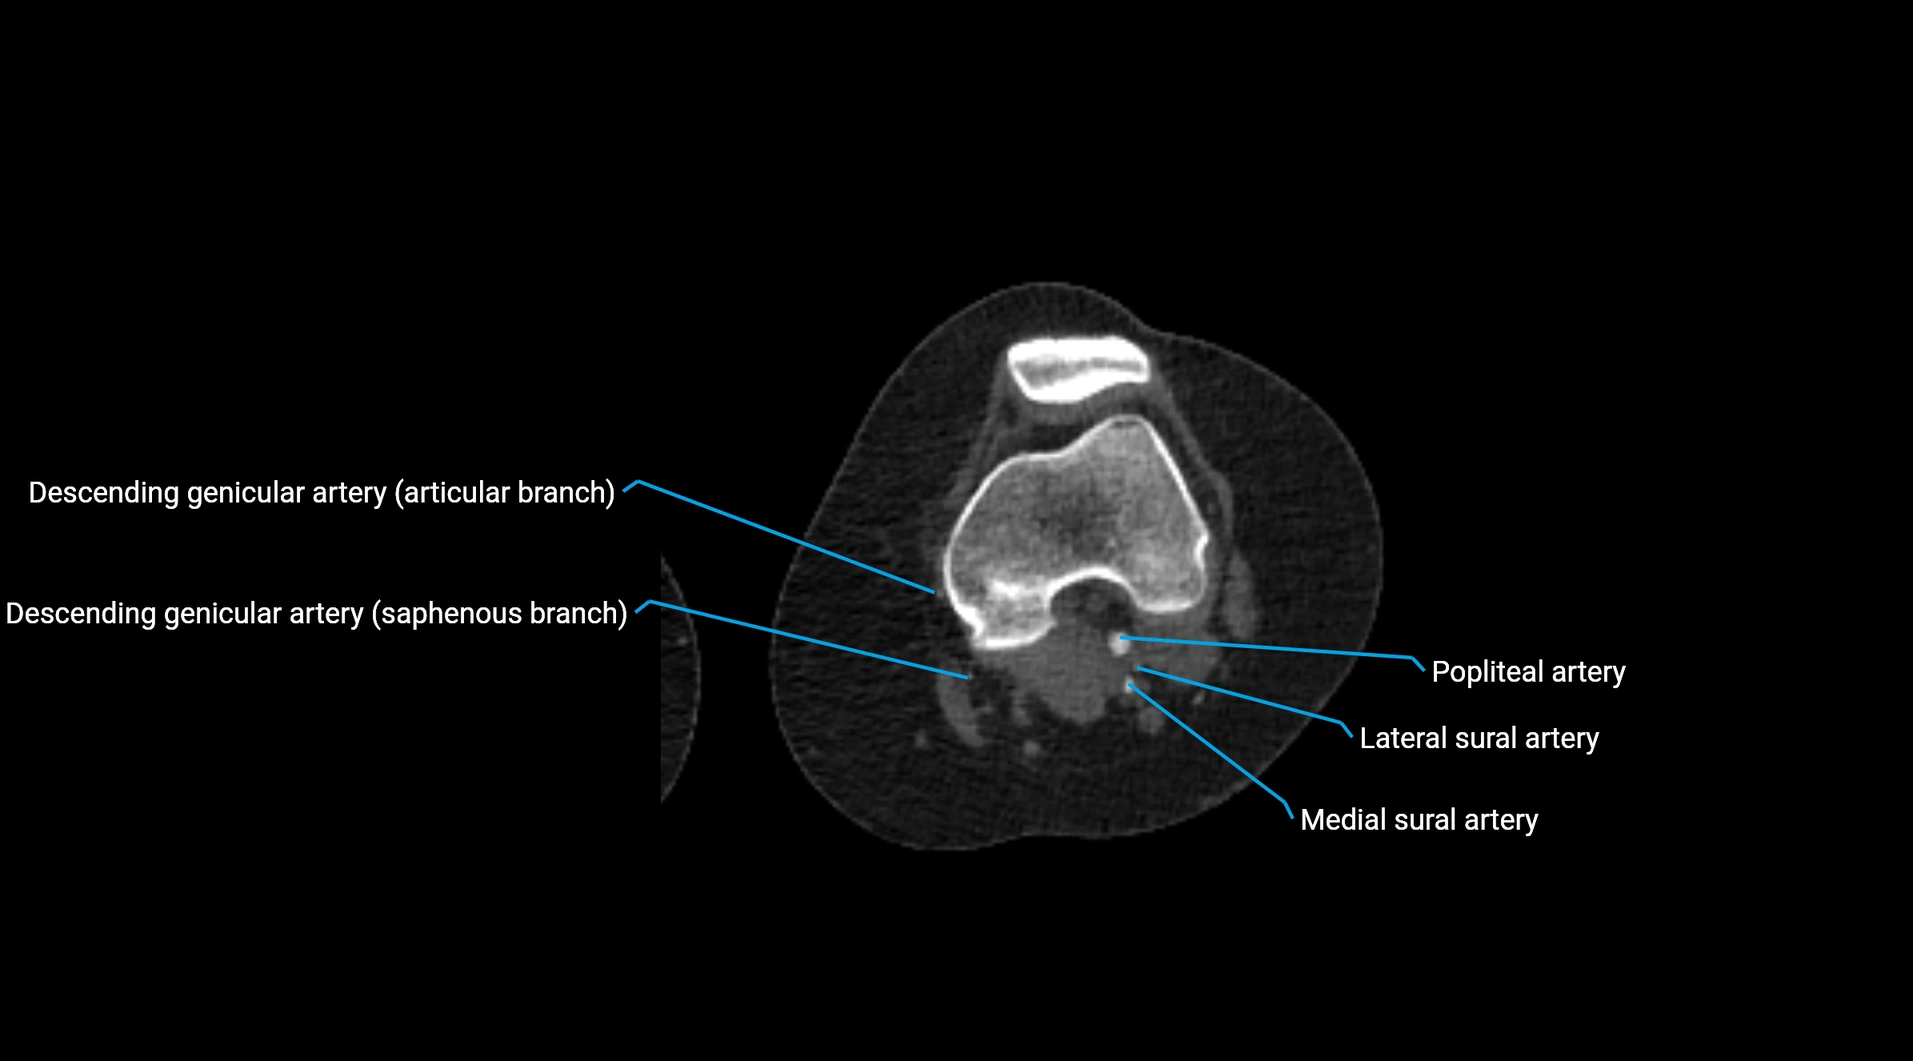

CT images

image